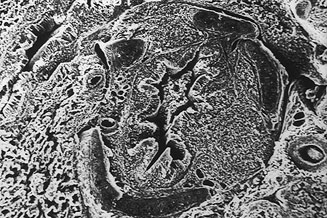

Microscopía electrónica. Corte transversal de un bronquio con proliferacion del BALT. 50X. ®